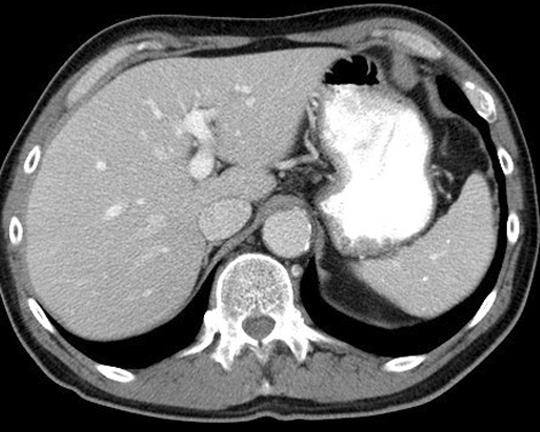

Identify the diaphragm. Click the image for labeling.